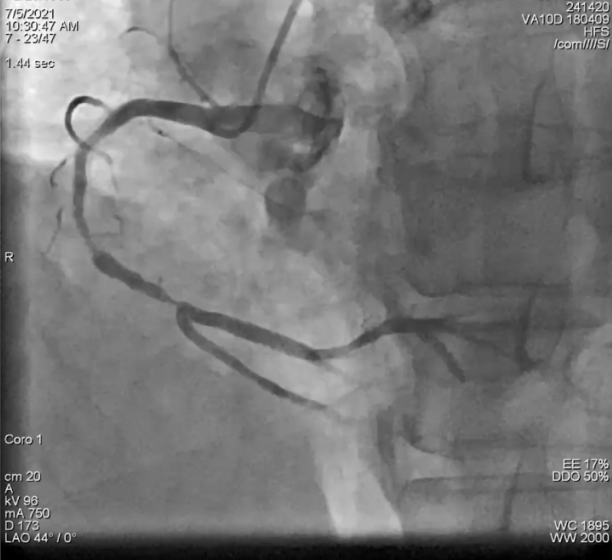

右冠造影结果

此次手术的患者为61岁男性,主因活动后胸闷、胸痛8年余,加重半月入院。患者8年前有急性心梗病史,分别于前降支及右冠植入3枚支架。此次入院造影可见右冠近端支架通畅,中至远段弥漫性狭窄,最重85%,后降支远段节段性狭窄60%。左主干无异常,前降支支架通畅,回旋支近端节段性狭窄80%。